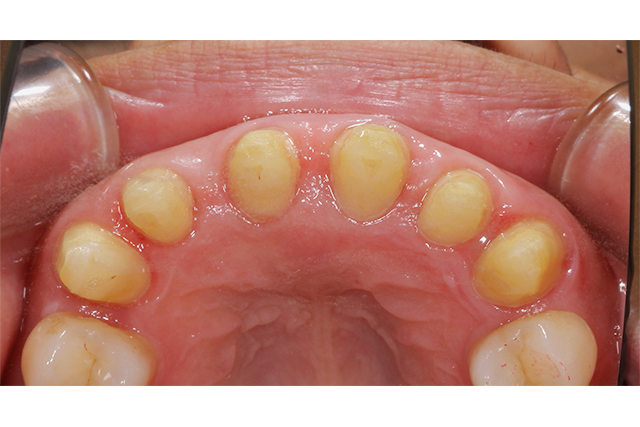

施術中

こちらは土台を形成している段階です。治療方法自体は、セラミックなどの保険適用のものと同様です。

前歯の隙間が気になり、保険適用での治療を希望されました。今回は、保険適用の CAD/CAM冠(キャドキャム冠) を用いた治療を行いました。 CAD/CAM冠 は白い被せものです。従来、虫歯治療などで被せものをする場合、保険診療では銀歯が一般的でしたが、CAD/CAM冠 を採用することで、保険適用内で自然な白い歯を実現できるようになりました。